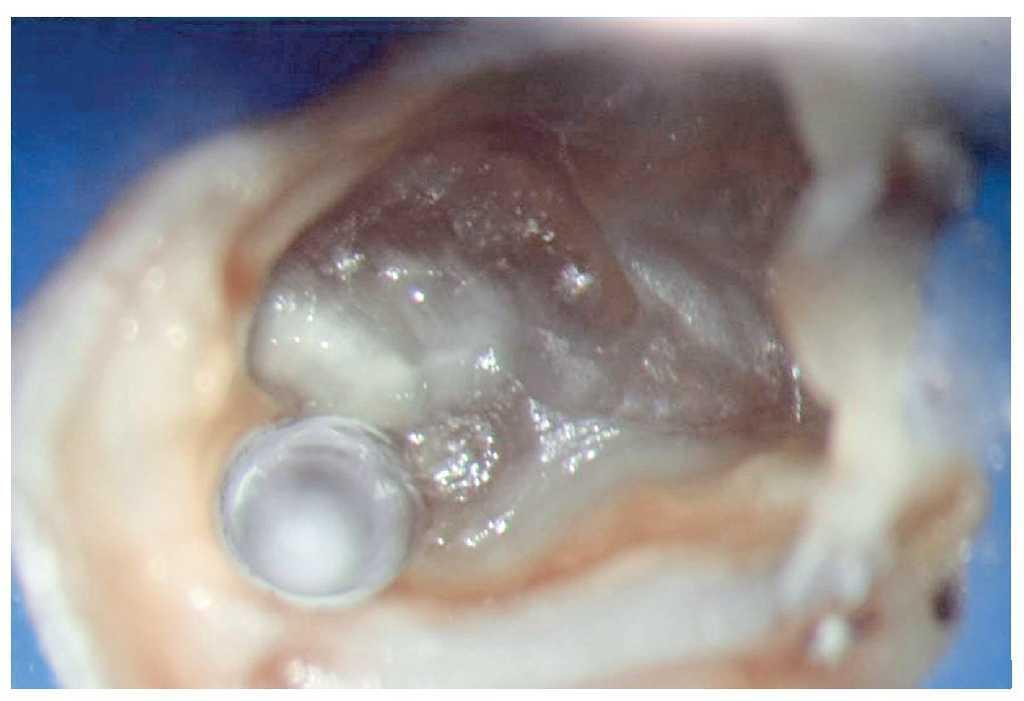

Figura 9h. Aplicación de MTA con uso de vibraciones ultrasónicas indirectas.

Esta técnica requiere tomar precauciones especiales en los casos de ápice abierto, dado que existe la posibilidad de paso de grandes cantidades de MTA al tejido periapical9. Después de introducir y condensar los primeros milímetros de MTA en la zona apical, se recomienda realizar un control radiográfico para evaluar la profundidad de adaptación y la densidad de obturación (fig. 9h).